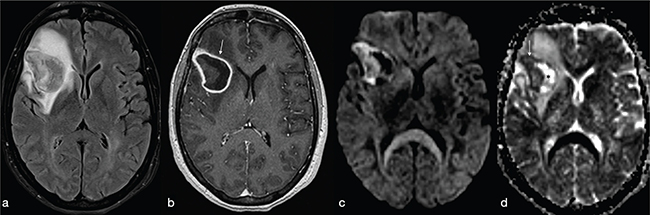

FIG 3. A 45-Year-Old Man with Pyogenic Abscess Surfacing the Left Parietal Lobe Cortex. A roundish mass with a core of necrotic-cystic degeneration (a–b) showing restricted diffusion on ADC maps (c) and diffuse surrounding vasogenic oedema (a–c) with irregular rim-enhancement (d) is shown. FLAIR-T2w (b) high signal within the subarachnoid spaces reveals rupture of abscess into the subarachnoid space (black arrows in b). Meningeal involvement is also appreciable after i.v. administration of Gd (white arrows in d).

FIG 4. A 54-Year-Old Woman with Multiple Pyogenic Abscesses Involving the Right Thalamus and Right Temporal Region. The abscesses show a thin capsule on T2w (a) binding a core of restricted diffusion (asterisk in b) with correspnding low signal in ADC maps (c). Smooth ring enhancement on gadolinium-enhanced T1w (d) is present. Satellite abscesses (black and white arrows in a and d respectively) give a polylobulated appearance.

After intravenous injection of gadolinium (Gd), a variable degree of contrast-enhancement of the capsule can be detected (Figure 5), depending on the evolutional stage of the abscess.7 A well-defined ring-enhancement can be detected only in the late evolutive stage of the BA. Due to the higher vascularity, the peripheral enhancement of BAs is thicker along the outer margin compared to the inner margin (Figure 6).9